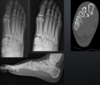

what type of fracture?

Pylon

Infications for foot ankle CT

Fx surgical planning Post op, healing comps or non unions tarsal soalitions cortical tumors gout

fx?

calc

45

talar fx

46

lisfranc

47

??

tarsal coalition